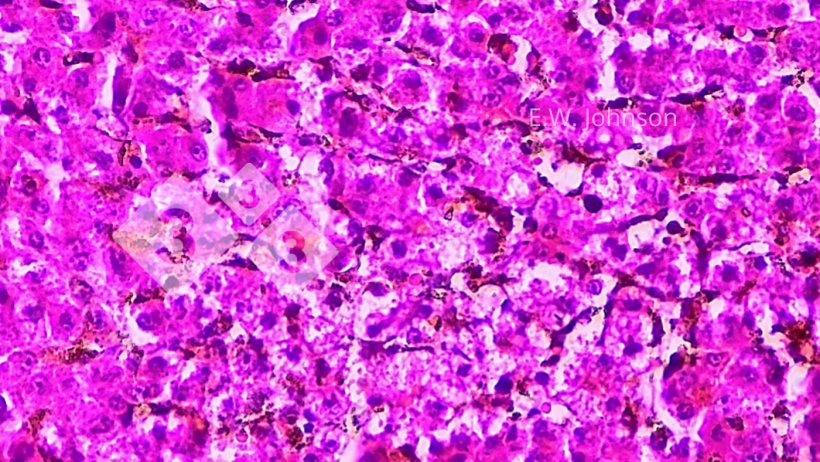

L'esame microscopico del cervello rivela meningoencefalite con cuffia (cuffing) perivascolare e gliosi (immagine 2) e infiltrazione delle meningi con cellule infiammatorie miste mononucleate e polimorfonucleate (immagine 3).

Si osserva necrosi focale nel fegato e corpi inclusi anfofilici intranucleari nel tessuto circostante le aree di necrosi (immagine 4). Viene fatta una diagnosi presuntiva della malattia di Aujeszky (AD Aujeszky's Disease).